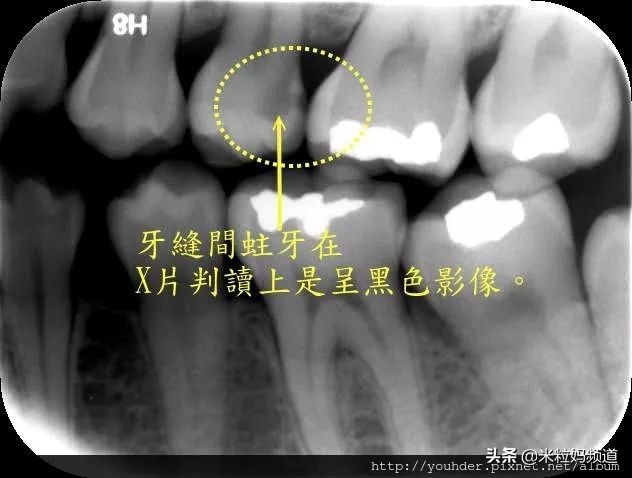

牙缝

牙缝容易蛀牙就很好理解了,不但容易卡食物,而且食物塞在缝隙里,牙刷也束手无策,根本刷不出来;更糟糕的是,肉眼还不容易发现,要借助X光才能知道看清楚牙缝里到底有没有蛀牙。